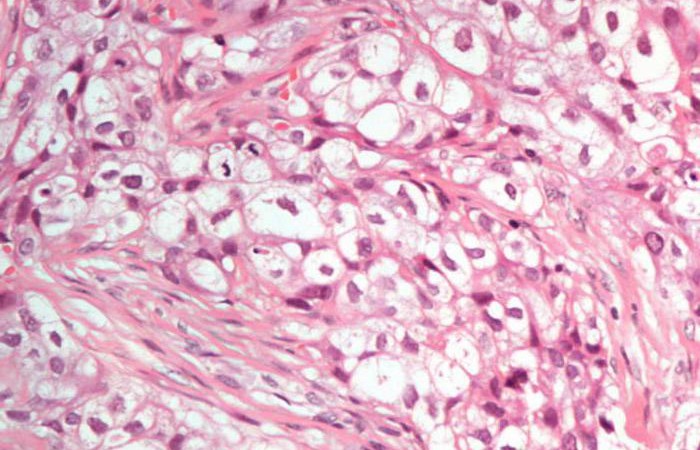

СогласенРак предстательной железы